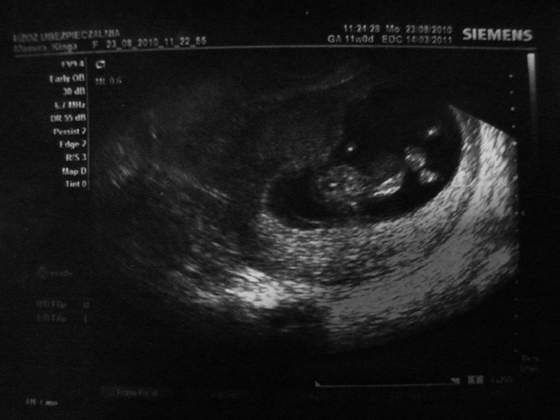

Ja wstawiam foto mojego szkraba :)

Mam nadzieję że widać ok :)